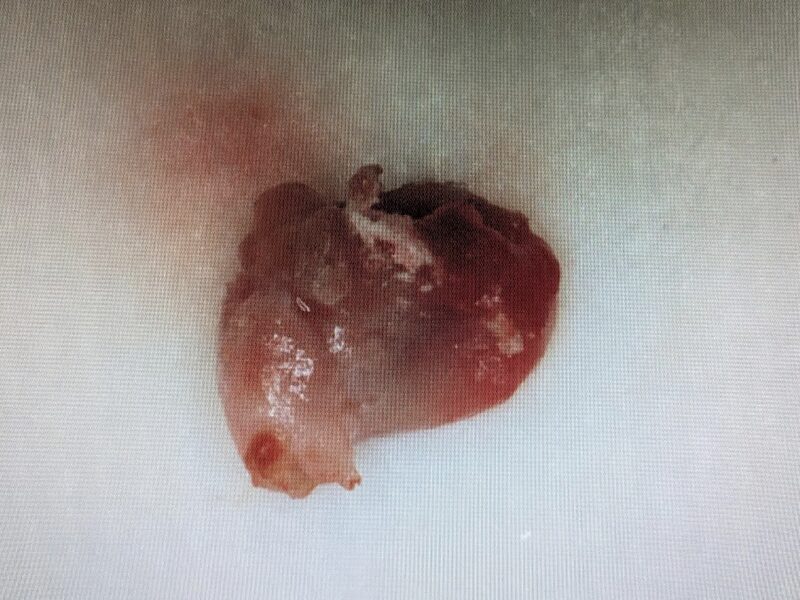

嚢胞を摘出します。

摘出された嚢胞です。